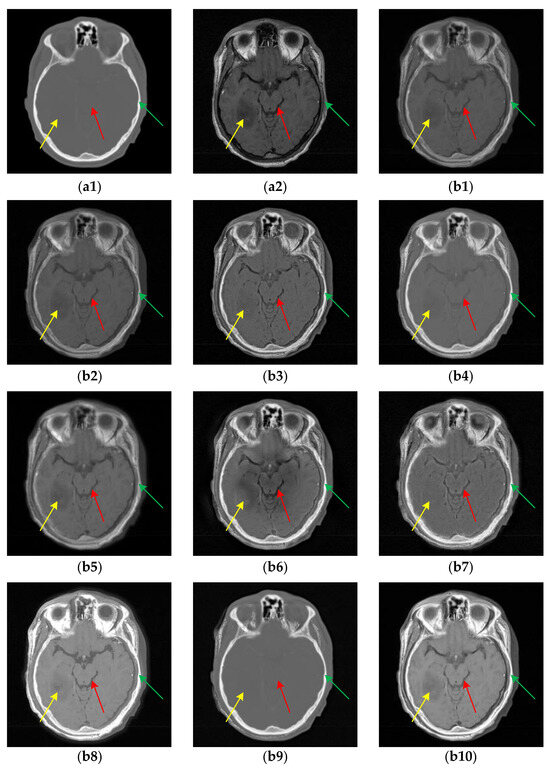

Figure 5. The results of all algorithms on the multi-modal image pairs from Atlas dataset. (a1) Source T1 image; (a2) Source T2 image; (b1) U2Fusion; (b2) DenseFuse; (b3) IFCNN; (b4) NestFuse; (b5) RFN-Nest; (b6) PAPCNN; (b7) ReLP; (b8) TIF; (b9) CDDFuse; (b10) CIRF.

The fusion results of multi-modal MR (i.e., T1 and T2) image pairs from the Atlas dataset are shown in Figure 5. Generally, except for TIF, CDDFuse and CIRF, the brightness and intensity of all other algorithms are insufficient. Specifically, from the areas marked by the red boxes, the upper parts of the brainstem are blurred or missing in the fused results of U2Fusion, DenseFuse, RFN-Nest, PAPCNN, ReLP and CDDFuse. Additionally, as labeled by the green boxes, except for CDDFuse and CIRF, all other methods produce blurry and incomplete boundaries of the occipital lobe. By comparison, the CIRF algorithm performs better than other algorithms in terms of edge preservation.